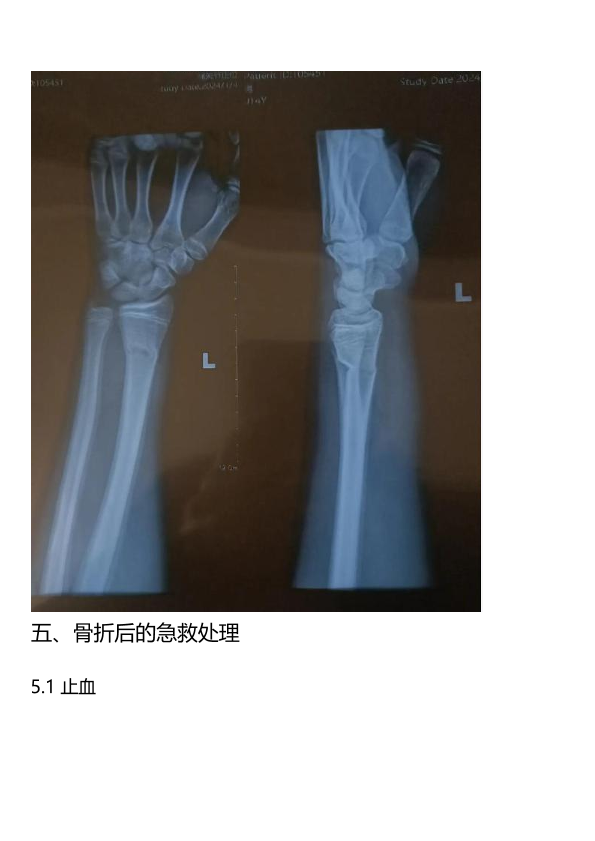

骨折科普知识